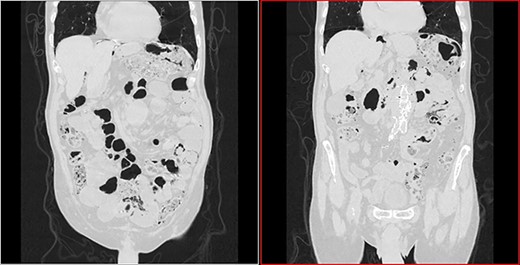

An 87-year-old male patient came to the radiology department to perform an abdominal computed tomography (CT) for follow-up of a bladder urothelial carcinoma. Upon CT evaluation, diffuse intestinal pneumatosis associated with pneumoperitoneum was identified on the exam (Fig. 1). The patient was called to return promptly to the hospital.

Sagittal CT image in lung window: (arrow) pneumoperitoneum and (arrow head) ‘bubbles’ within the walls of small intestine segment and the adjacent mesentery, featuring pneumatosis cystoides intestinalis and mesenteric.